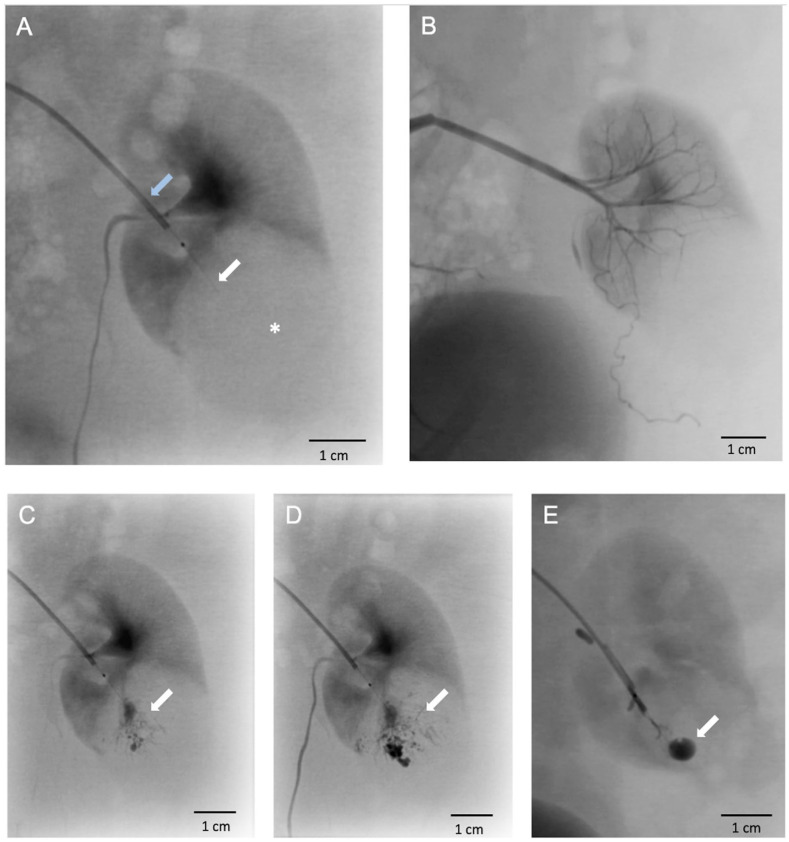

{"title":"VX2 兔子模型中的跨血管壁细胞移植、移植物和肿瘤通路。","authors":"Victoria Lövljung, Mathias Waldén, Mikael Sandell, Peter Damberg, Staffan Holmin, Fabian Arnberg Sandor","doi":"10.1177/09636897251313678","DOIUrl":null,"url":null,"abstract":"<p><p>The trans-vessel wall device (TW-device) is a new endovascular tool for precise and safe delivery of various payloads (cells, viral, modified RNA, chemotherapy, growth factors) in oncology and regenerative medicine. The twofold aim of this study was to assess cell engraftment and tumor growth using the TW-device for endovascular transplantation and to evaluate its ability to directly access solid tumors. We used the VX2 model in the rabbit kidney to compare percutaneously implanted fresh VX2 cells with TW-device injections of cryopreserved VX2 cells. We demonstrated the feasibility of endovascular transplantation (<i>n</i> = 7) of tumor cells, achieving a 57.1% engraftment rate despite cryopreservation, comparable with 70% for percutaneous delivery of fresh cells (<i>n</i> = 10). Re-access using the TW-device was 100% successful (<i>n</i> = 11) with super-selective intratumoral contrast administration without complications. In conclusion, endovascular transplantation of VX2 cells using the TW-device resulted in proliferating cell grafts in the rabbit kidney establishing functional proof that cells indeed survive handling, preparation, and device passage. We also show the TW-device is able to access solid tumor parenchyma allowing precise intraparenchymal administration.This proof-of-concept study open up possibilities for repeated direct parenchymal injections via the endovascular route in any hard to reach organ.</p>","PeriodicalId":9721,"journal":{"name":"Cell Transplantation","volume":"34 ","pages":"9636897251313678"},"PeriodicalIF":3.2000,"publicationDate":"2025-01-01","publicationTypes":"Journal Article","fieldsOfStudy":null,"isOpenAccess":false,"openAccessPdf":"https://www.ncbi.nlm.nih.gov/pmc/articles/PMC11773539/pdf/","citationCount":"0","resultStr":"{\"title\":\"Trans-Vessel Wall Cell Transplantation, Engraftment, and Tumor Access in the VX2 Rabbit Model.\",\"authors\":\"Victoria Lövljung, Mathias Waldén, Mikael Sandell, Peter Damberg, Staffan Holmin, Fabian Arnberg Sandor\",\"doi\":\"10.1177/09636897251313678\",\"DOIUrl\":null,\"url\":null,\"abstract\":\"<p><p>The trans-vessel wall device (TW-device) is a new endovascular tool for precise and safe delivery of various payloads (cells, viral, modified RNA, chemotherapy, growth factors) in oncology and regenerative medicine. The twofold aim of this study was to assess cell engraftment and tumor growth using the TW-device for endovascular transplantation and to evaluate its ability to directly access solid tumors. We used the VX2 model in the rabbit kidney to compare percutaneously implanted fresh VX2 cells with TW-device injections of cryopreserved VX2 cells. We demonstrated the feasibility of endovascular transplantation (<i>n</i> = 7) of tumor cells, achieving a 57.1% engraftment rate despite cryopreservation, comparable with 70% for percutaneous delivery of fresh cells (<i>n</i> = 10). Re-access using the TW-device was 100% successful (<i>n</i> = 11) with super-selective intratumoral contrast administration without complications. In conclusion, endovascular transplantation of VX2 cells using the TW-device resulted in proliferating cell grafts in the rabbit kidney establishing functional proof that cells indeed survive handling, preparation, and device passage. We also show the TW-device is able to access solid tumor parenchyma allowing precise intraparenchymal administration.This proof-of-concept study open up possibilities for repeated direct parenchymal injections via the endovascular route in any hard to reach organ.</p>\",\"PeriodicalId\":9721,\"journal\":{\"name\":\"Cell Transplantation\",\"volume\":\"34 \",\"pages\":\"9636897251313678\"},\"PeriodicalIF\":3.2000,\"publicationDate\":\"2025-01-01\",\"publicationTypes\":\"Journal Article\",\"fieldsOfStudy\":null,\"isOpenAccess\":false,\"openAccessPdf\":\"https://www.ncbi.nlm.nih.gov/pmc/articles/PMC11773539/pdf/\",\"citationCount\":\"0\",\"resultStr\":null,\"platform\":\"Semanticscholar\",\"paperid\":null,\"PeriodicalName\":\"Cell Transplantation\",\"FirstCategoryId\":\"3\",\"ListUrlMain\":\"https://doi.org/10.1177/09636897251313678\",\"RegionNum\":4,\"RegionCategory\":\"医学\",\"ArticlePicture\":[],\"TitleCN\":null,\"AbstractTextCN\":null,\"PMCID\":null,\"EPubDate\":\"\",\"PubModel\":\"\",\"JCR\":\"Q3\",\"JCRName\":\"CELL & TISSUE ENGINEERING\",\"Score\":null,\"Total\":0}","platform":"Semanticscholar","paperid":null,"PeriodicalName":"Cell Transplantation","FirstCategoryId":"3","ListUrlMain":"https://doi.org/10.1177/09636897251313678","RegionNum":4,"RegionCategory":"医学","ArticlePicture":[],"TitleCN":null,"AbstractTextCN":null,"PMCID":null,"EPubDate":"","PubModel":"","JCR":"Q3","JCRName":"CELL & TISSUE ENGINEERING","Score":null,"Total":0}

跨血管壁装置(tr -device)是一种新的血管内工具,用于肿瘤和再生医学中各种有效载荷(细胞,病毒,修饰RNA,化疗,生长因子)的精确和安全输送。本研究的双重目的是评估使用tw -装置进行血管内移植的细胞植入和肿瘤生长,并评估其直接接触实体瘤的能力。我们使用兔肾VX2模型,比较经皮植入新鲜VX2细胞与tw装置注射冷冻保存的VX2细胞。我们证明了肿瘤细胞血管内移植(n = 7)的可行性,尽管冷冻保存,植入率仍为57.1%,而经皮输送新鲜细胞的植入率为70% (n = 10)。使用tw -装置重新进入的成功率为100% (n = 11),超选择性肿瘤内造影剂施用无并发症。综上所述,使用TW-device对VX2细胞进行血管内移植,在兔肾中产生了增殖的细胞移植物,证明了细胞在处理、制备和设备传递过程中确实存活了下来。我们也展示了tw -装置能够进入实体瘤实质,允许精确的实质内给药。这一概念验证研究开辟了通过血管内途径在任何难以到达的器官中重复直接实质注射的可能性。

The trans-vessel wall device (TW-device) is a new endovascular tool for precise and safe delivery of various payloads (cells, viral, modified RNA, chemotherapy, growth factors) in oncology and regenerative medicine. The twofold aim of this study was to assess cell engraftment and tumor growth using the TW-device for endovascular transplantation and to evaluate its ability to directly access solid tumors. We used the VX2 model in the rabbit kidney to compare percutaneously implanted fresh VX2 cells with TW-device injections of cryopreserved VX2 cells. We demonstrated the feasibility of endovascular transplantation (n = 7) of tumor cells, achieving a 57.1% engraftment rate despite cryopreservation, comparable with 70% for percutaneous delivery of fresh cells (n = 10). Re-access using the TW-device was 100% successful (n = 11) with super-selective intratumoral contrast administration without complications. In conclusion, endovascular transplantation of VX2 cells using the TW-device resulted in proliferating cell grafts in the rabbit kidney establishing functional proof that cells indeed survive handling, preparation, and device passage. We also show the TW-device is able to access solid tumor parenchyma allowing precise intraparenchymal administration.This proof-of-concept study open up possibilities for repeated direct parenchymal injections via the endovascular route in any hard to reach organ.